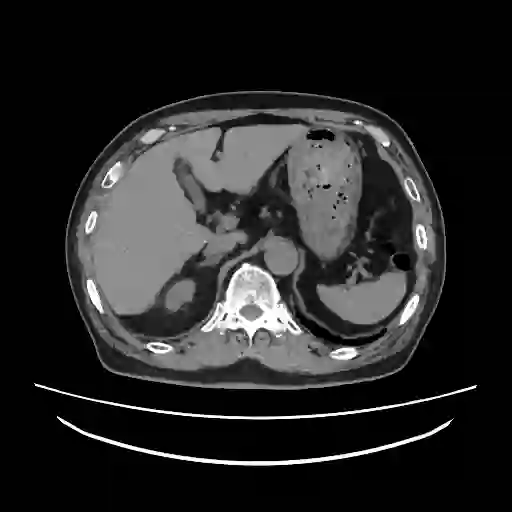

We propose a novel continual self-supervised learning (CSSL) framework for simultaneously learning diverse features from multi-window-obtained chest computed tomography (CT) images and ensuring data privacy. Achieving a robust and highly generalizable model in medical image diagnosis is challenging, mainly because of issues, such as the scarcity of large-scale, accurately annotated datasets and domain shifts inherent to dynamic healthcare environments. Specifically, in chest CT, these domain shifts often arise from differences in window settings, which are optimized for distinct clinical purposes. Previous CSSL frameworks often mitigated domain shift by reusing past data, a typically impractical approach owing to privacy constraints. Our approach addresses these challenges by effectively capturing the relationship between previously learned knowledge and new information across different training stages through continual pretraining on unlabeled images. Specifically, by incorporating a latent replay-based mechanism into CSSL, our method mitigates catastrophic forgetting due to domain shifts during continual pretraining while ensuring data privacy. Additionally, we introduce a feature distillation technique that integrates Wasserstein distance-based knowledge distillation (WKD) and batch-knowledge ensemble (BKE), enhancing the ability of the model to learn meaningful, domain-shift-robust representations. Finally, we validate our approach using chest CT images obtained across two different window settings, demonstrating superior performance compared with other approaches.

翻译:我们提出了一种新颖的持续自监督学习框架,用于同时从多窗位获取的胸部计算机断层扫描图像中学习多样化特征,并确保数据隐私。在医学影像诊断中构建鲁棒且高度可泛化的模型具有挑战性,主要源于大规模精确标注数据集的稀缺性以及动态医疗环境中固有的领域偏移问题。具体而言,在胸部CT中,这些领域偏移常由针对不同临床目的优化的窗位设置差异引起。以往的持续自监督学习框架通常通过复用历史数据来缓解领域偏移,但由于隐私限制,这种方法往往不切实际。我们的方法通过在未标注图像上进行持续预训练,有效捕捉不同训练阶段中已有知识与新信息之间的关联,从而应对这些挑战。具体而言,通过将基于潜在重放的机制融入持续自监督学习,我们的方法在确保数据隐私的同时,缓解了持续预训练中因领域偏移导致的灾难性遗忘。此外,我们引入了一种特征蒸馏技术,该技术整合了基于Wasserstein距离的知识蒸馏与批次知识集成,增强了模型学习具有意义且对领域偏移鲁棒的表征能力。最后,我们使用两种不同窗位设置获取的胸部CT图像验证了所提方法,结果表明其性能优于其他现有方法。